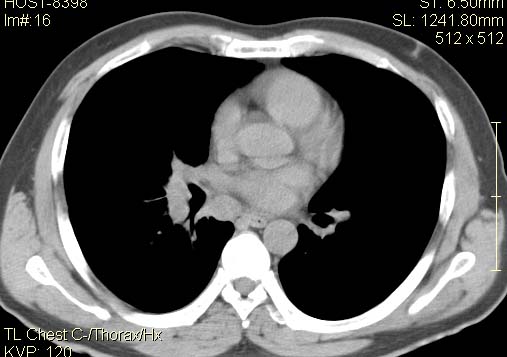

以下是引用qc80012345在2007-4-17 12:33:00的发言:[br]右肺下叶周围型肺癌伴肺门及纵隔内淋巴结转移;比较清楚。

以下是引用qingyuan在2007-4-17 14:19:00的发言:[br]右肺下叶外侧后段胸膜下区节结样病变、分叶、内可见空洞,壁厚薄不均,胸膜凹陷、肺门周围区纹理增粗、僵硬、并近似小结节样改变,肺门区软组织节结、纵膈淋巴结肿大,患者病史长、抗炎治疗无好转炎性改变基本排除,考虑:右肺下叶周围型肺癌伴纵膈及右肺门区淋巴结转移、肺内淋巴管受侵。